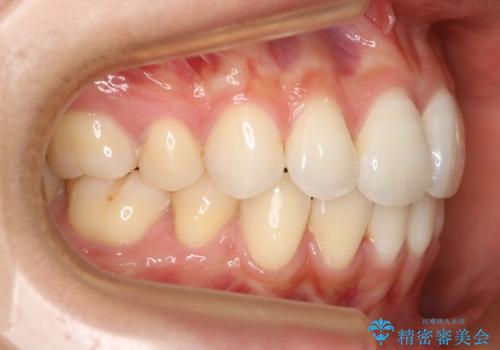

- 治療計画

ハーフリンガルとは上顎を裏側、下顎を表側のワイヤー装置で治療する場合をいいます。

フルリンガル(上下とも裏側)で治療するよりも費用が抑えられ、治療期間も伸びにくい傾向にあります。また、下顎の舌側に装置がないおかげで口内炎や発音障害もフルリンガルに比べて少ないとされています。